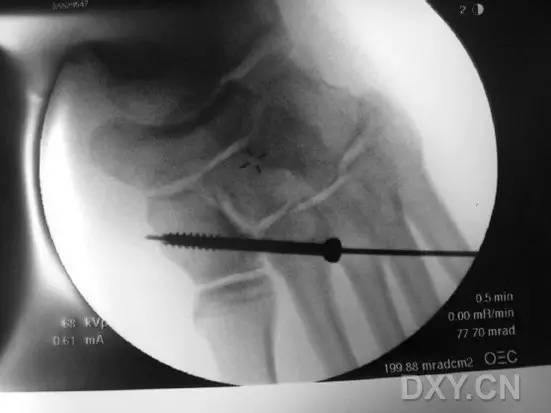

应用一把大号持骨钳把持固定于第 2 跖骨基底外侧面(经原手术切口或在该部位做一小切口,然后钝性分离、显露第 2 跖骨外侧面骨质)和内侧楔骨内侧面(在该部位做一小切口,然后钝性分离、显露内侧楔骨内侧面骨质)之间,以维持复位(图 3)。

图 3. 术中 X 线透视下,在中足经 Lisfranc 关节置入持骨钳,以维持固定损伤复位